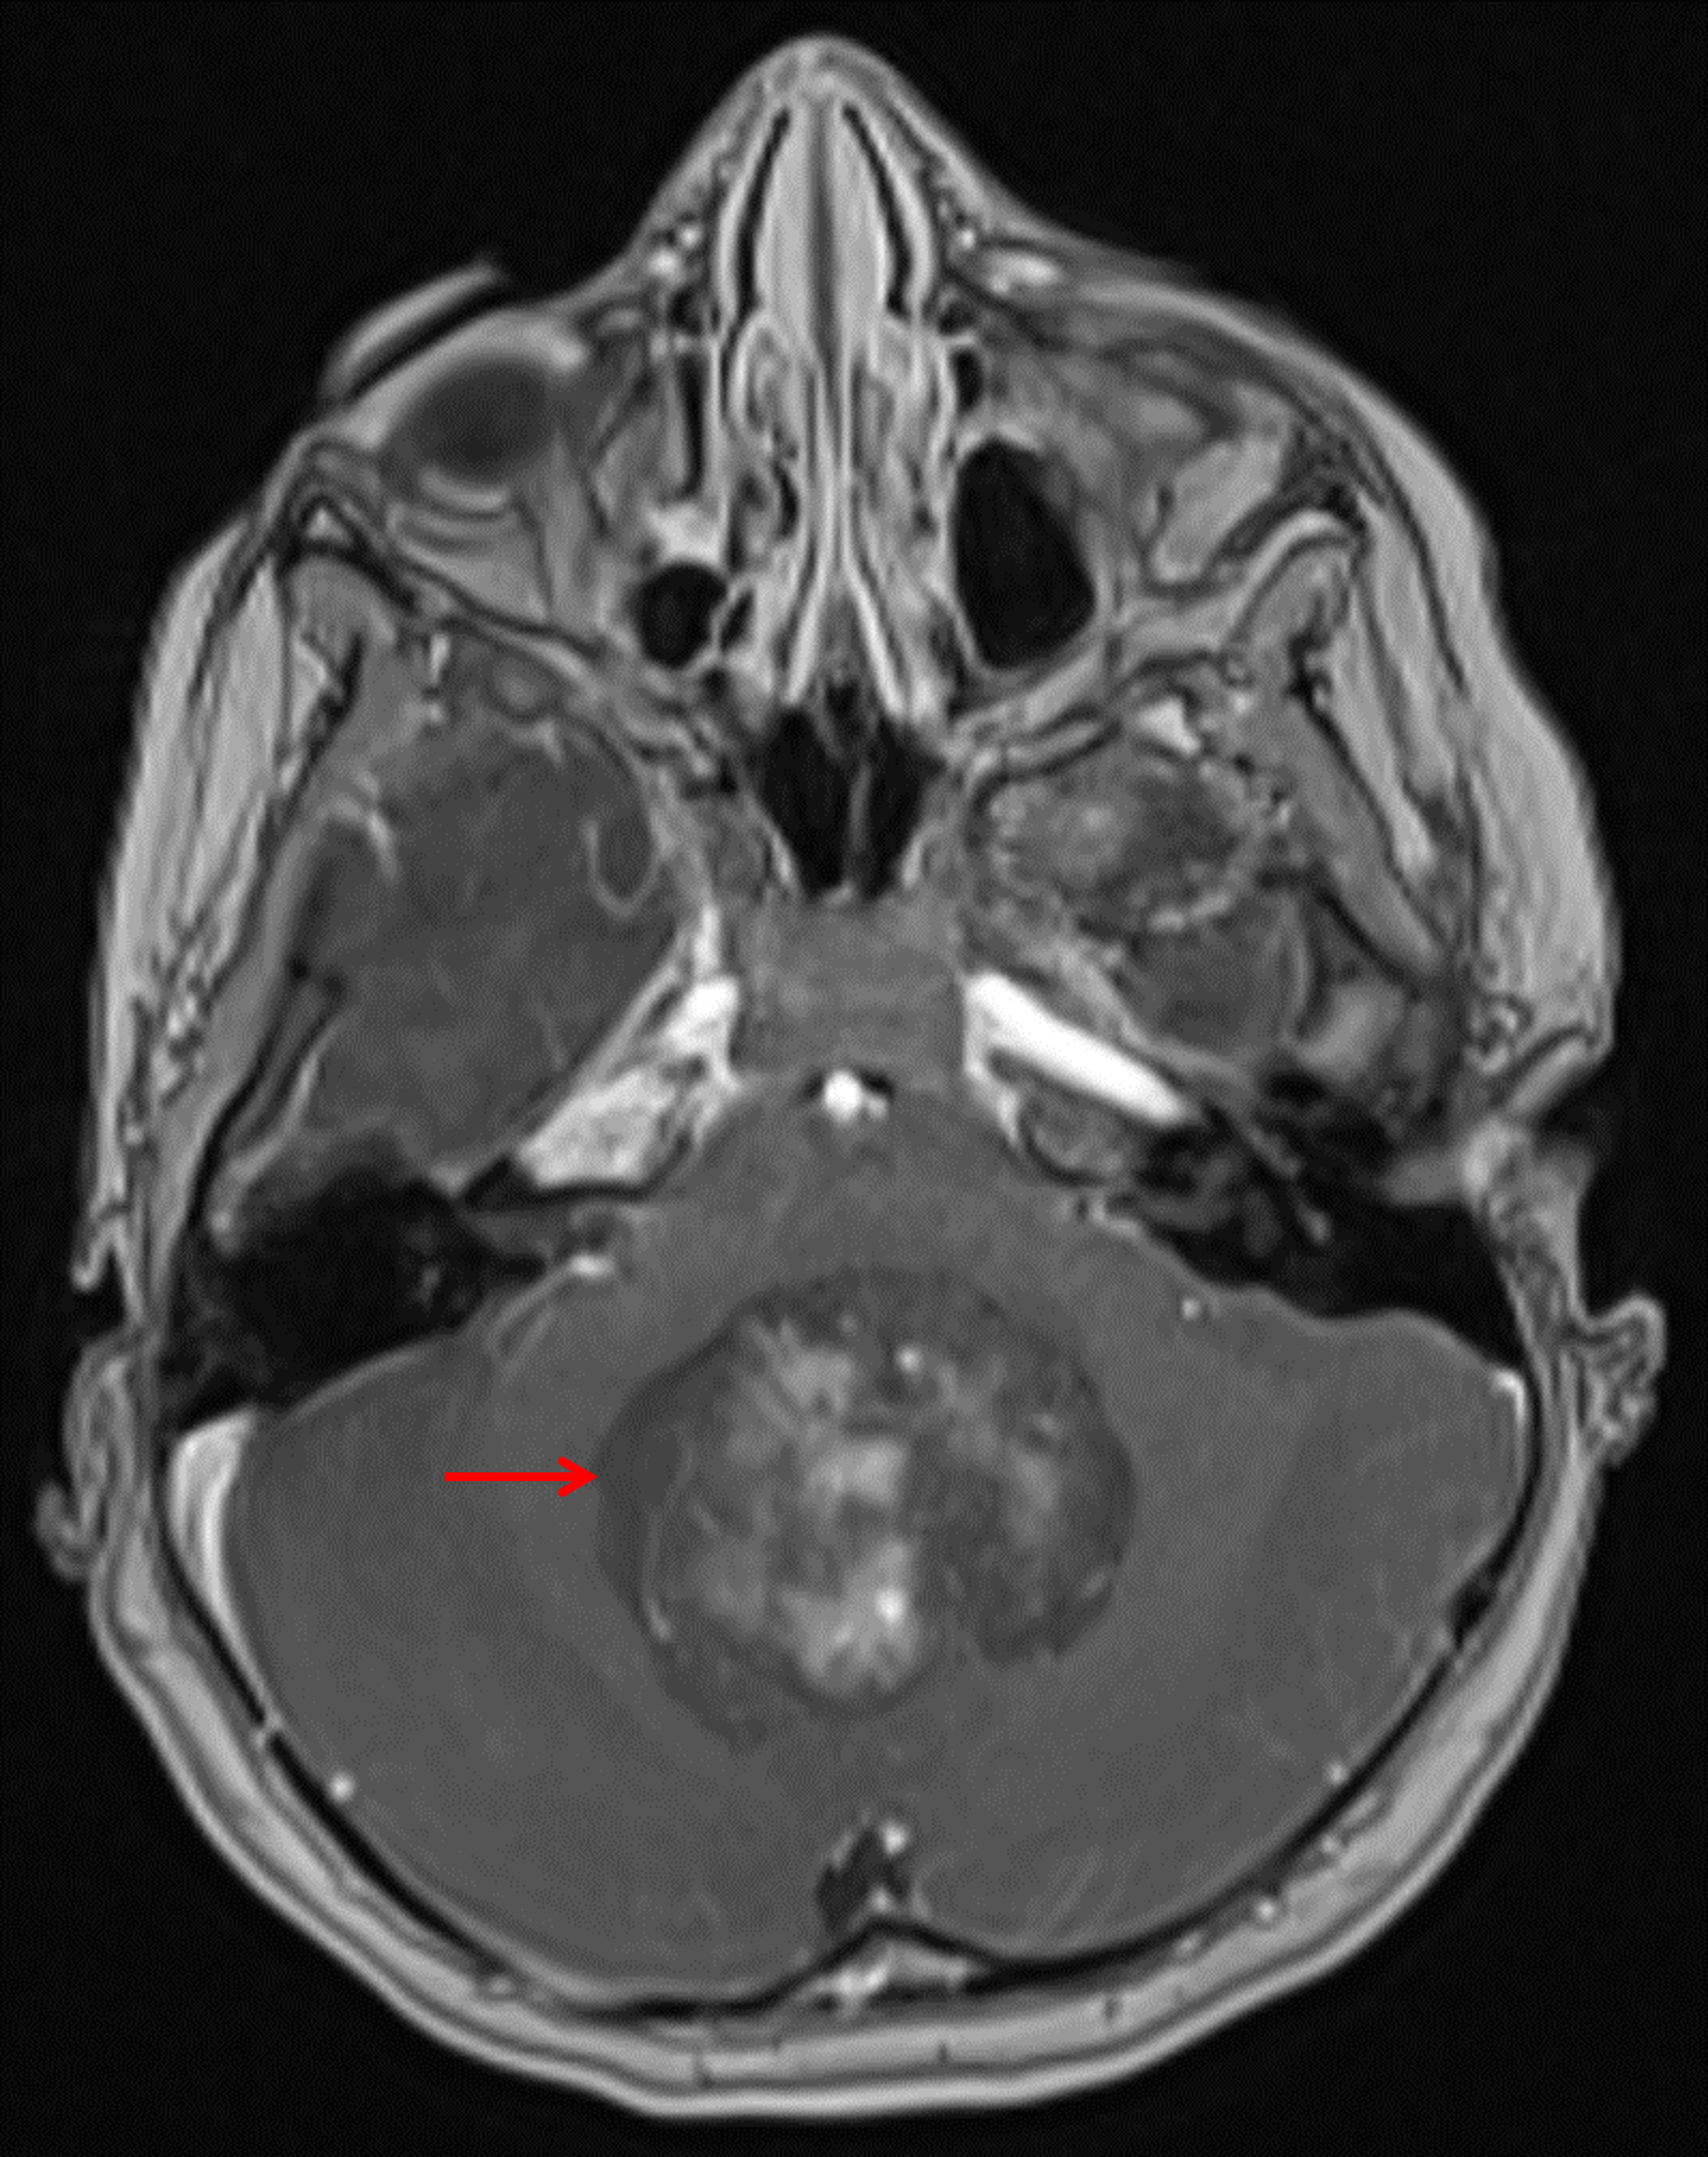

Age: 6

Sex: Female

Indication: Headache

Medulloblastoma